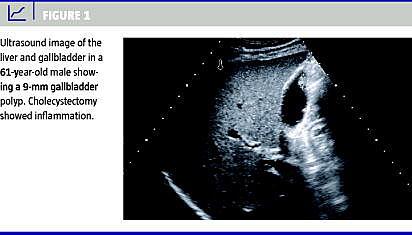

Galdeblærepolypper (GP) er et hyppigt, tilfældigt og sjældent symptomgivende fund ved abdominale ultralydskanninger (US) og findes i stigende grad med den tiltagende brug af US. Patienter med GP større end 10 mm eller størrelsestilvækst i GP bliver typisk henvist til kolecystektomi pga. den øgede risiko for malignitet. Ved små GP på mindre end 10 mm bliver patienten oftest indkaldt til kontrol-US med henblik på tilvækst, men der er ikke enighed om håndteringen af små GP. Formålet med dette studie var at undersøge størrelsesfordelingen af GP og udfaldet af opfølgende US for små GP.

I alt 203 patienter i alderen 19-95 år (medianværdi 54 år) med GP blev inkluderet i studiet. Der var 89 (44%) mænd og 114 (56%) kvinder. Størrelsen af GP varierede fra 2 mm til 40 mm med en middelværdi på 5 mm. Hos 143 patienter (70%) var størrelsen af GP mindre end 6 mm. Den første kontrol-US blev gennemført hos 120 patienter (59%), og kun 31 (15%) gennemførte det fulde toårs US-opfølgningsprogram. Størrelsen af GP var uændret hos 100 patienter, aftagende hos fem patienter, tiltagende hos otte og helt regredieret hos 15 patienter. Af de 203 patienter med GP fik 13 patienter foretaget kolecystektomi, og heriblandt var der ingen neoplastiske eller maligne GP.

Cancer i galdeblære og galdeveje er en relativ sjælden lidelse med en årlig incidens på ca. 200 i Danmark. Derimod er galdeblærepolypper en meget hyppig tilstand, som forventes hos ca. 5% af den raske befolkning. I overensstemmelse med andre studier fandt vi, at hovedparten af ultralyddefinerede GP var små, sjældent tiltagende i størrelse og uden maligne forandringer hos de kolecystektomerede. For at nedsætte den unødvendige kontrol-US af de mange patienter med små GP foreslås en ændring i gældende retningslinjer, således at der ikke fremover foretages opfølgende US på GP, der er mindre end 6 mm. Alternativt kan det overvejes, om intervallerne mellem kontrol-US af de små GP skal øges.